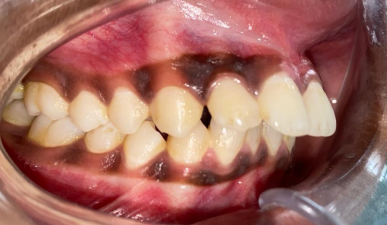

Intra-oral examination revealed proclination of maxillary anterior teeth (Figure 01) and multiple linear cracks or deep grooves measuring 1-2 cms on the middle 1/3rd and anterior 2/3rd of the tongue (Figure 2). It was asymptomatic and non-tender on palpation. A provisional diagnosis of skeletodental malocclusion and a fissured tongue was established. But the parents and the child were more concerned about the correction of maligned teeth. The relevant photographs, study models and x-rays were advised in order to plan for the correction of malocclusion.

Figure 1